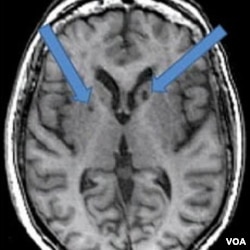

Hasil MRI atas otak pasien yang pernah terkena stroke dua kali. Panah menunjukkan adanya bintik-bintik gelap yang dulunya adalah sel-sel sehat yang mati akibat gumpalan darah yang masuk ke otak.

Pada hasil pemindaian pasien stroke, tampak lubang gelap berisi cairan. Psikolog syaraf Adam Brickman pada Fakultas Kedokteran Universitas Columbia, mengatakan ada bintik-bintik gelap yang dulunya adalah sel-sel sehat yang mati akibat gumpalan darah yang masuk ke otak.

Hasil pemindaian MRI menunjukkan 25 persen peserta penelitian itu terkena stroke ringan. Mereka ternyata juga tidak mendapat nilai baik pada tes daya ingat. Peneliti berharap untuk terus mencermati kelompok itu dalam setahun ke depan, guna mengamati adanya tanda-tanda penyakit Alzheimer, yang merupakan bentuk paling serius dari demensia